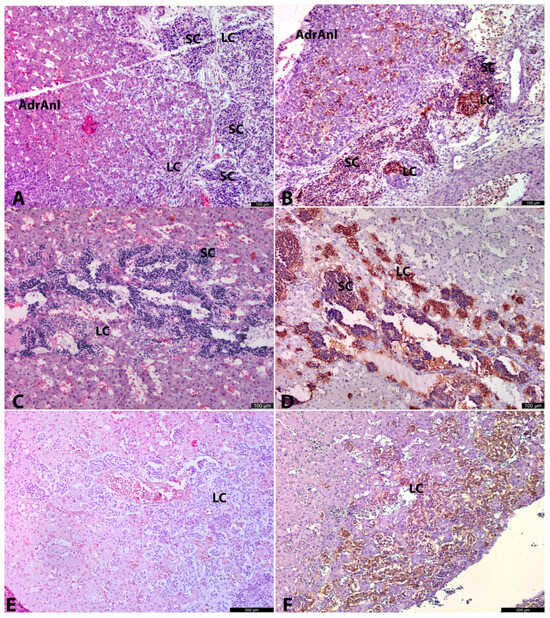

Figure 2. Adrenal anlages in 3 age groups. AdrAnl—adrenal anlage, LC—large cells, SC—small cells. The left column of micrographs shows sections stained with hematoxylin and eosin. The right column shows IHC with TH, 11–12 g.w. human prefetus (No. 4), adrenal anlage with adjacent tissues. Large clear cells (LCs) are seen intermingling between oxyphilic cortical cells. Conglomerates of SCs and LSc (to a lesser extent) are located in close proximity to the adrenal anlage. Nerve fibers are connecting small cell structures and invading cortical anlage (A). At 11–12 g.w. human prefetus (No. 4), adrenal anlage with adjacent tissues. LCs both inside and outside the adrenal anlage are highly positive for TH. SCs are weakly positive for TH (B). At 20–21 g.w. human fetus (No. 10), adrenal anlage. Abundant rounded clusters of SCs are seen along with peripherally located LCs. A lot of vessels and/or vessel-like spaces/cavities or “cisterns” are found between small and large cell groups. In many of the lumens of these vessels/vessel-like spaces erythrocytes are seen (C). At 20–21 g.w. human fetus (No. 10), adrenal anlage. Rounded clusters of SCs with weak cytoplasmic TH positivity are seen along with intensively positive groups of LCs. “Cisterns” in the SC groups are also seen (D). At 25–26 g.w. human fetus (No. 14), adrenal gland. LCs are the predominant cell type of the AM (E). At 25–26 g.w. human fetus (No. 14), adrenal gland. LCs are highly positive for TH (F).